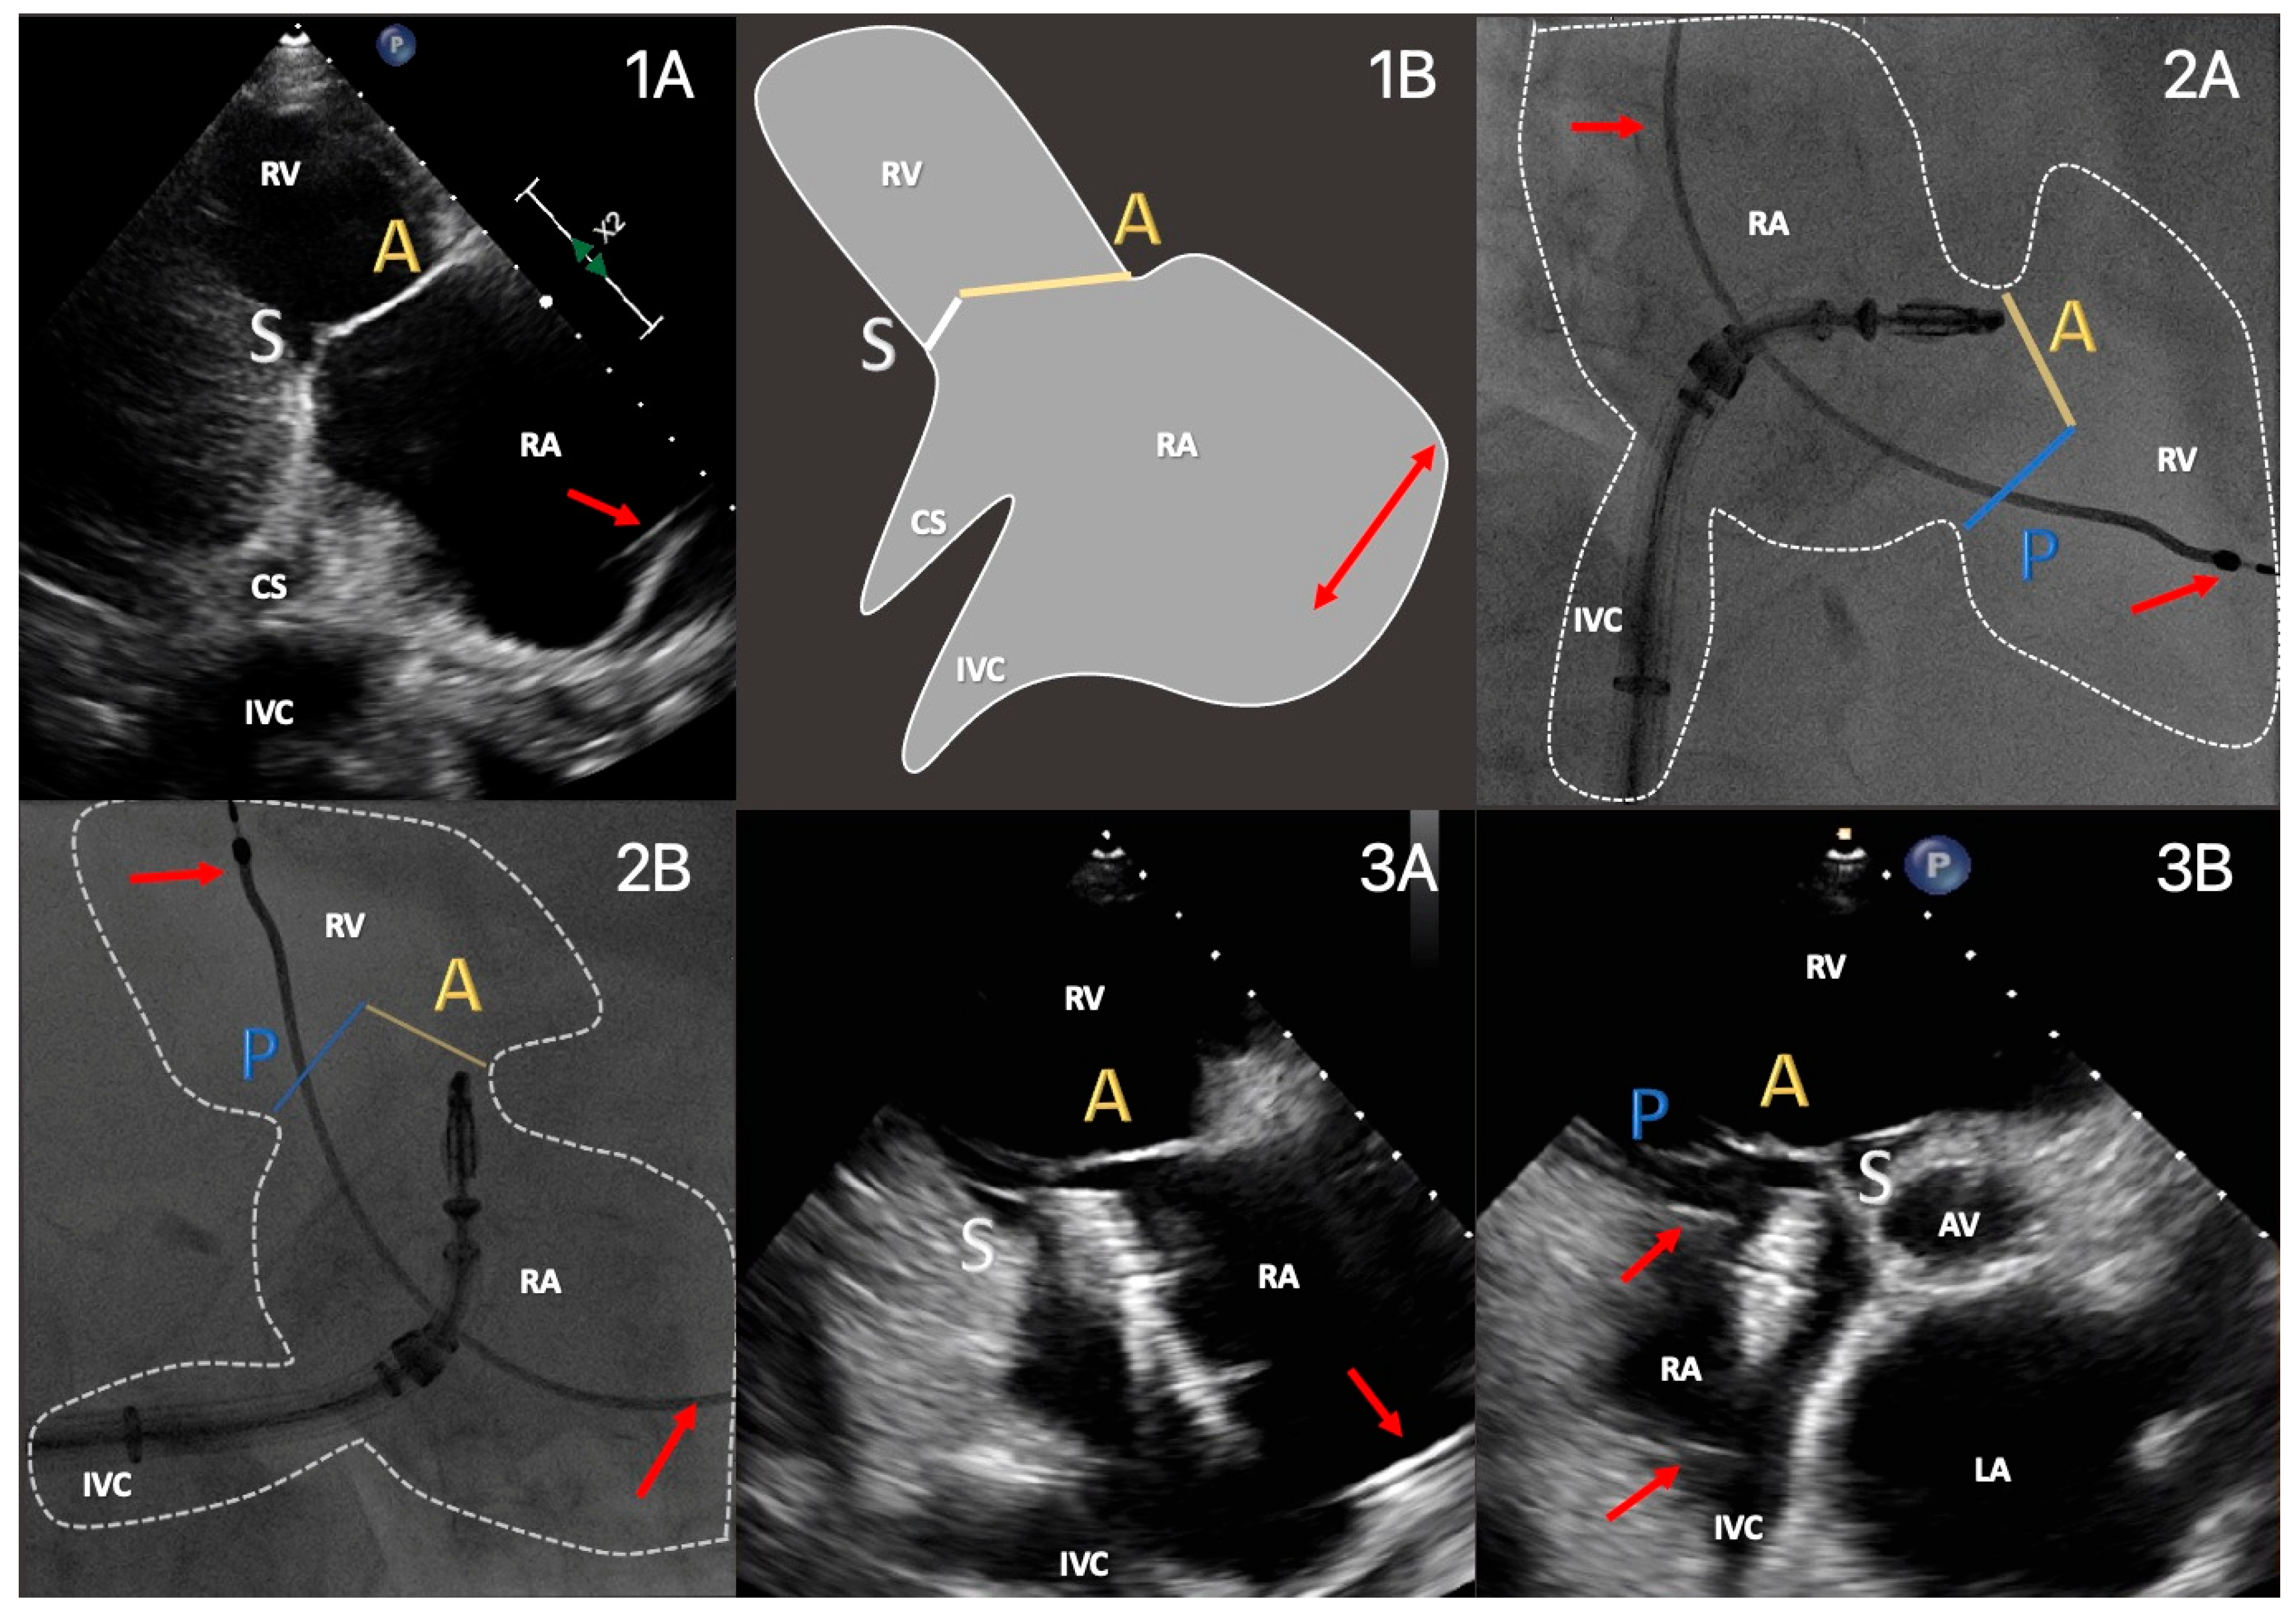

2.4. Imaging Protocol

2.5. Procedural Protocol